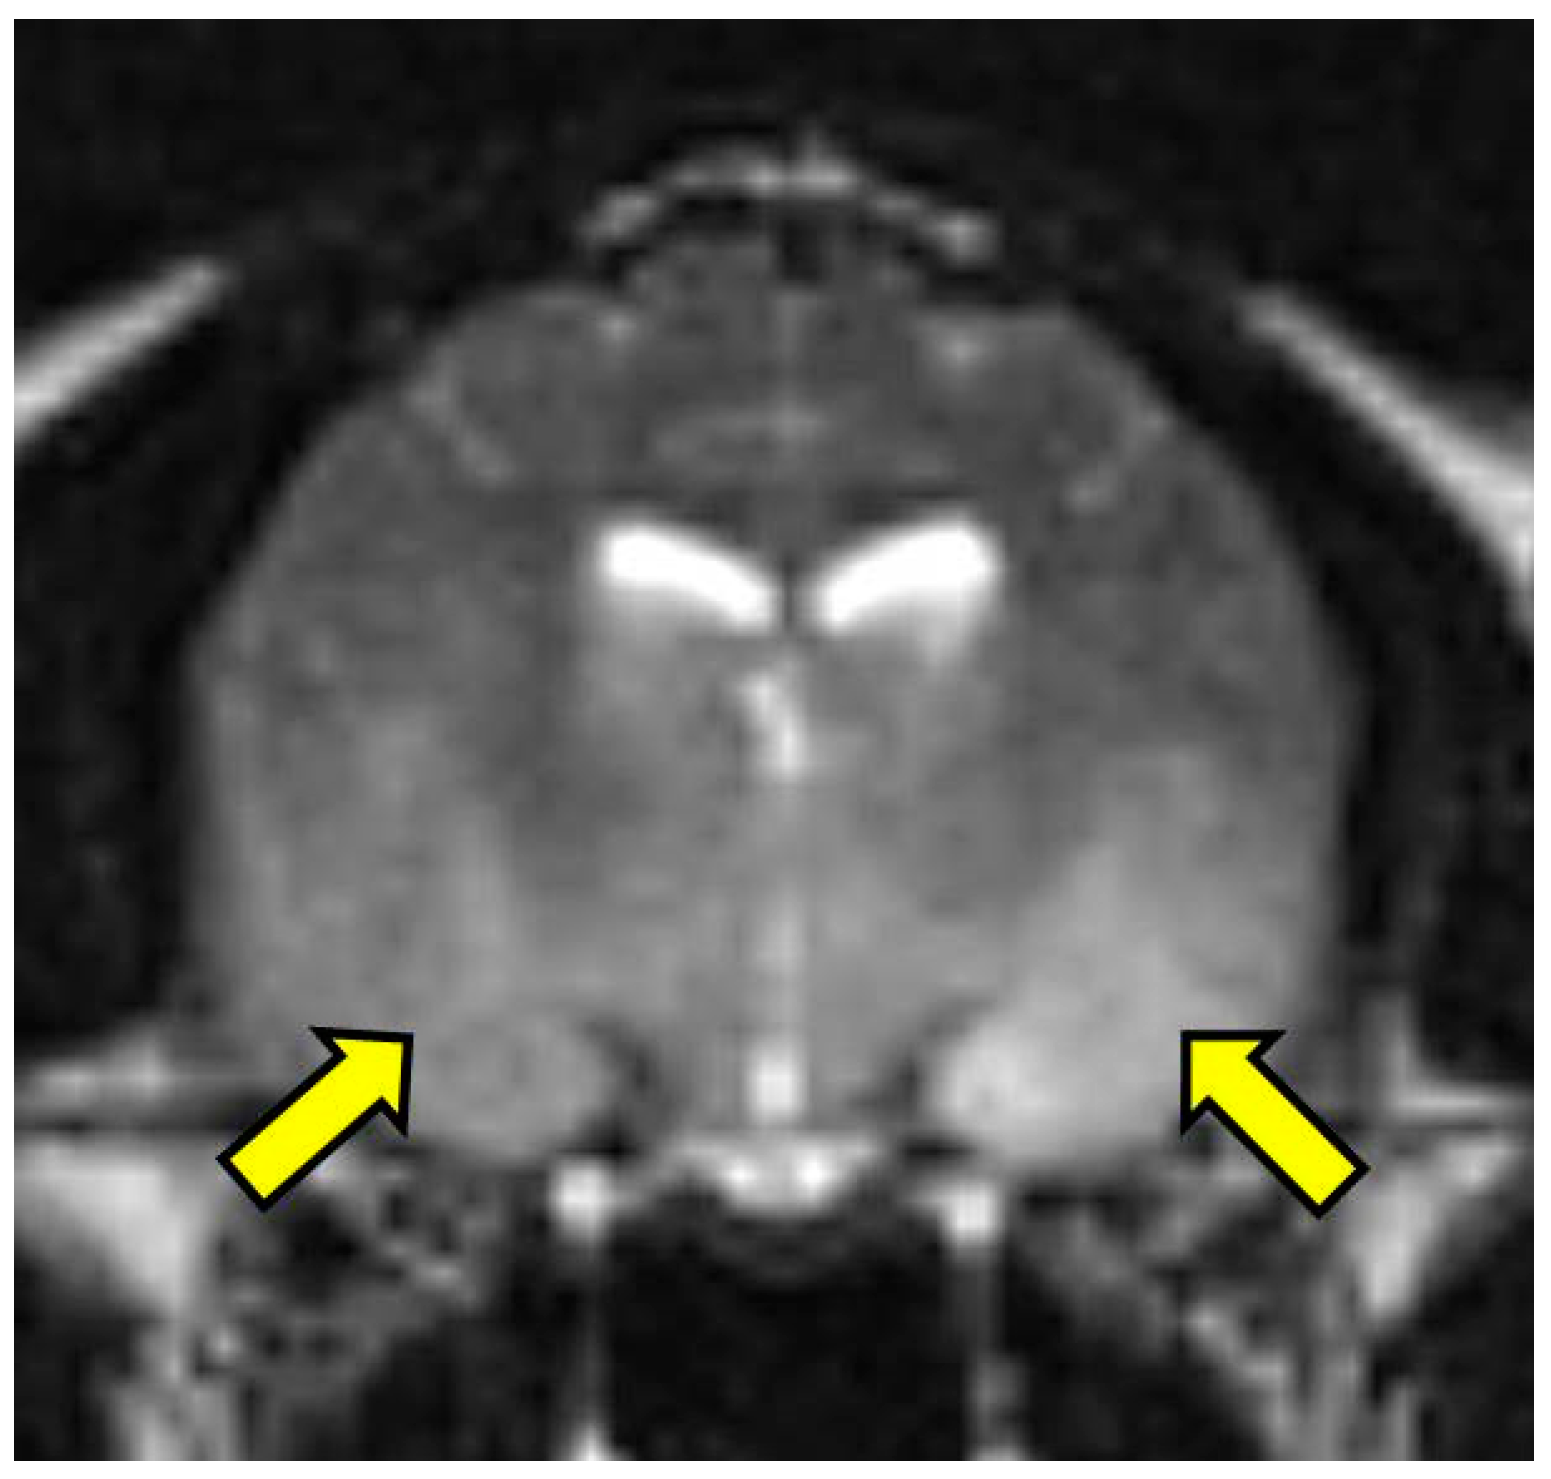

On MRI scanning of the brain, an intra-axial, diffuse, non-contrast-enhancing, T2-weighted, hyperintense mass effect extending through the ventral forebrain (including the piriform and temporal lobes, thalamus, crus cerebri, and colliculi) and midbrain (Figure 1) was found. The caudal aspects of the cerebellum were compressed against the occipital bone. There was also caudal transtentorial herniation of the midbrain and herniation of the cerebellar vermis through the foramen magnum (Figure 2). A linear, T2 hyperintense area was present in the dorsal aspect of the C2-C5 spinal cord; transverse images of this area showed dilation of the central canal, T2 hyperintensity, and non-contrast-enhancing T1 hypointensity in the dorsal spinal cord, most consistent with syrinx formation. Based on clinical findings and MRI results, differential diagnoses included multicentric neoplasia or an infectious etiology such as feline infectious peritonitis (FIP), feline immunodeficiency virus (FIV), feline leukemia virus (FeLV), or cryptococcosis. Due to poor prognosis and rapid clinical decline, the cat was humanely euthanized.

Figure 1. T2 weighted transverse image at the level of the piriform lobe showing the ill-defined, ventrally distributed T2-weighted hyperintensity affecting the piriform lobes, temporal lobes, hypothalamus, and portions of the caudal colliculus and internal capsule (arrows). MRI scan.